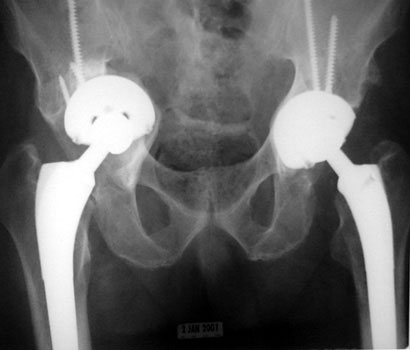

COMPONENT MIGRATION

ACETABULAR CUP

ACETABULAR COMPONENT

Progressive protrusio and tilt